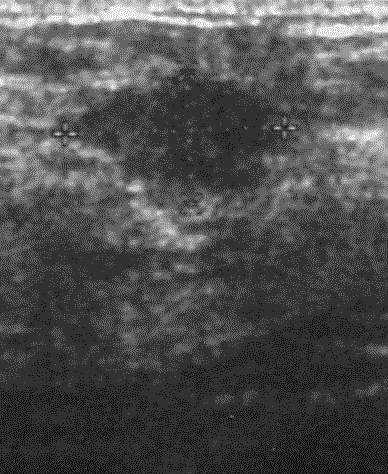

The target dataset was developed from 35 breast ultrasound scans that were segmented by an image-processing expert with extensive experience in breast lesion segmentation (the second author). The images, collected from the Web, are of different dimensions, ranging from to pixels (Figure 3, images resized for sake of illustration). These are the same images used to introduce EFIS originally [1].

Ultrasound images are generally difficult to segment, primarily due to the presence of speckle noise and low level of local contrast. It should be noted that the segmentation of ultrasound actually does require a complete processing chain, (including proper preprocessing and post-processing steps). However, the purpose of using these images was solely to demonstrate that the accuracy of the segmentation can be increased with the application of SC-EFIS.